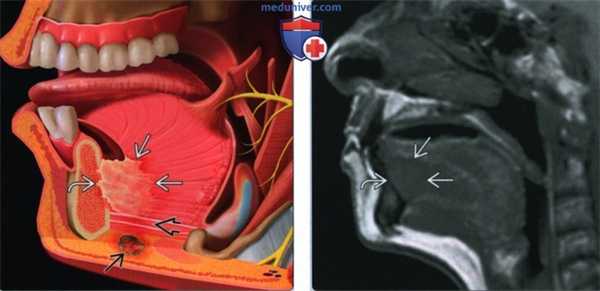

(Слева) На рисунке показано наиболее частое расположение ПКР дна полости рта: в пределах 2 см от средней линии в передних отделах. При анализе изображений важно оценить распространение опухоли каудально с инвазией подбородочно-язычной и челюстно-подъязычной мышц, кзади по направлению к корню языка, и кпереди или латерально с инвазией нижней челюсти. С этой целью может потребоваться и МРТ, и КТ. Другой целью методов визуализации является оценка вторичного поражения лимфатических узлов.

(Справа) При МРТ Т1ВИ в сагиттальной проекции визуализируется объемное образование с сигналом низкой интенсивности по сравнению с мышцами языка, прилежащее вплотную к нижней челюсти по средней линии.

(Слева) При МРТ Т1ВИ С + FS в аксиальной проекции у этого же пациента не четко визуализируется объемное образование передних отделов дна полости рта, прорастающее в правую подъязычную железу. Обратите внимание на отсутствие кортикальной пластинки с гипоинтенсивным сигналом в прилежащих отделах нижней челюсти, что подтверждается и при КТ в костном окне. Патологически измененные лимфоузлы не определяются.

(Справа) На фото этого же пациента, полученном при клиническом обследовании, также видна опухоль в передних отделах дна полости рта. Фото позволяет оценить локализацию опухоли и подъязычных желез. На операции была подтверждена опухоль T4aN0 с инвазией нижней челюсти.

(Слева) При MPT Т2ВИ FS в аксиальной проекции визуализируется небольшая опухоль в боковых отделах языка справа, выглядящая как двояковыпуклый участок с сигналом повышенной интенсивности и с типичными нечеткими краями, недостигающий средней линии.

(Справа) Корональная томограмма (Т1ВИ С+ FS) этого же пациента, язва в боковых отделах языка накапливает контраст. Опухоль не распространяется книзу в подбородочно-язычную мышцу или в другие наружные мышцы языка, и не достигает срединно расположенной язычной перегородки. Была выполнена гемиглоссэктомия и селективная шейная лимфодиссекция, подтвердился ПКР (Т1 N0, первая стадия).

(Слева) При аксиальной КТ с КУ у курильщика 59 лете жалобами на болезненное уплотнение в языке, появившееся пять месяцев назад, в задних боковых отделах языка визуализируется изъязвленное объемное образование неправильной формы, интенсивно накапливающее контраст. На более каудальных томограммах был также выявлен единичный лимфоузел второго уровня.

(Справа) При корональной КТ с КУ определяется неравномерное контрастное усиление язвы. Отсутствуют признаки глубокой инфильтрации наружных мышц языка, опухоль не достигает средней линии. Была выполнена правосторонняя гемиглоссэктомия и модифицированная шейная лимфодиссекция, подтвердился ПКР T2N1 (третья стадия).

(Слева) При МРТ Т1ВИ С+ FS в корональной проекции в боковых отделах языка справа определяется большое объемное образование неправильной формы, накапливающее контраст во всех отделах за исключением центрального некроза. Опухоль вызывает инвазию подбородочно-язычной мышцы и пересекает среднюю линию.

(Справа) При МРТ Т2ВИ FS в аксиальной проекции, выполненной на уровне нижней стенки полости рта у этого же пациента, лучше видна зона опухолевой инфильтрации, распространяющаяся по направлению к нижней челюсти справа; тем не менее, признаки опухолевой инфильтрации костной ткани отсутствуют. Поскольку пациенту всего 31 год, была выполнена тотальная глоссэктомия и резекция нижней стенки полости рта, подтвердился ПКР T4aN2b (IVA стадия).